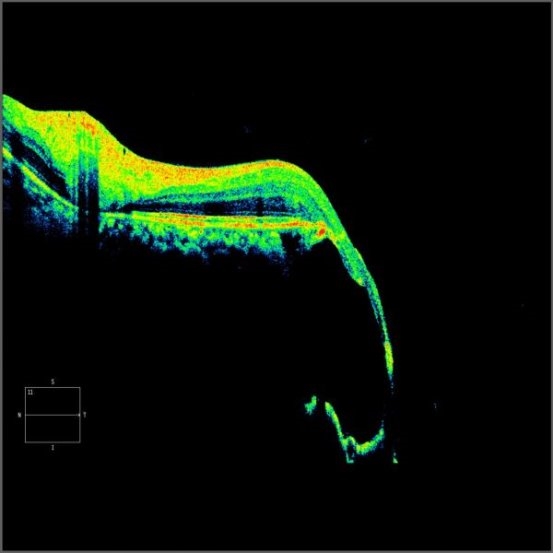

一张红黄绿的OCT(光学相干断层扫描),边缘呈断崖式垂落,显示黄斑部(视网膜视力最敏锐的位置,承担人90%的视力)视网膜脉络膜缺损。患者自由视力不佳,如今只有眼前指数(仅能判断近距离如眼前50cm或30cm处,手指的数量)的视力。

【黄斑部视网膜脉络膜缺损】